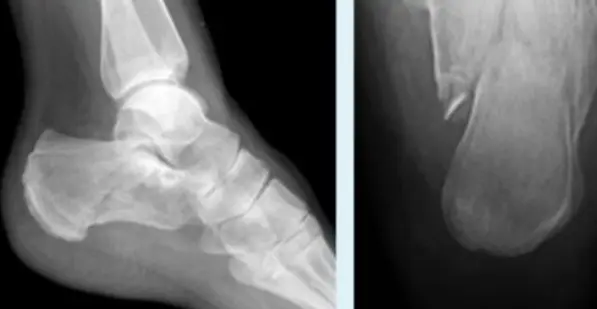

Ankle and Distal Lower Leg

Syndesmotic Injuries

A 17-year-old male had a high ankle sprain followed by pain in his leg. X-ray films were obtained. According to the attached X-ray, which structure has been injured?

- B. Syndesmosis ligament

Mortise View of the Ankle

Foot Injuries